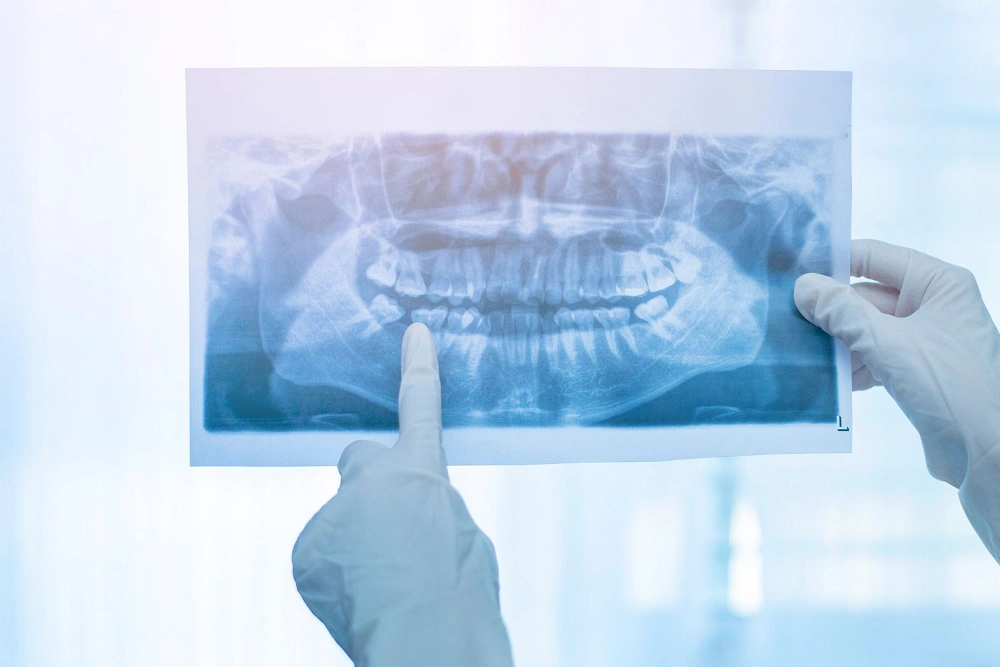

تصویربرداری با تکنیک بایت وینگ ابزار قدرتمندی برای دندانپزشکان هستند تا مشکلات دهان و دندان را با دقت بالا تشخیص دهند. یکی از اصلیترین کاربردهای این تصاویر، بررسی پوسیدگی بین دندانی است که معمولا با معاینه بالینی قابل مشاهده نیست. پوسیدگیها در تصاویر بایت وینگ به شکل مناطق تاریک بین دندانها ظاهر میشوند و دندانپزشک میتواند عمق و شدت پوسیدگی را تعیین کند. این اطلاعات به طراحی درمان دقیق و به موقع کمک میکند.

علاوه بر پوسیدگی، تصاویر بایت وینگ امکان بررسی ترمیمها و پرکردگیهای قبلی را فراهم میکنند. دندانپزشک میتواند وضعیت پرکردگیها، روکشها و دیگر ترمیمها را ارزیابی کند و هر گونه ترک، جدا شدن یا تحلیل را شناسایی کند. این قابلیت به پیشگیری از مشکلات پیچیده و کاهش نیاز به درمانهای پرهزینه کمک میکند.

تصاویر بایت وینگ همچنین برای ارزیابی استخوان و لثه کاربرد دارند. تحلیل استخوان بین دندانها و اطراف ریشهها به تشخیص بیماریهای پریودنتال و تحلیل استخوان کمک میکند. با بررسی تغییرات استخوان در تصاویر دورهای، دندانپزشک میتواند روند پیشرفت بیماری را تحت نظر داشته باشد و درمانهای پیشگیرانه انجام دهد.

علاوه بر کاربردهای تشخیصی، تفسیر تصاویر بایت وینگ به دندانپزشک امکان میدهد برنامه درمانی شخصیسازی شده ارائه دهد. با ترکیب اطلاعات پوسیدگی، وضعیت ترمیمها و سلامت استخوان و لثه، بهترین تصمیم درمانی برای هر بیمار اتخاذ میشود. این تکنیک نه تنها دقت تشخیص را افزایش میدهد، بلکه باعث اعتماد بیشتر بیمار به روند درمان میشود.